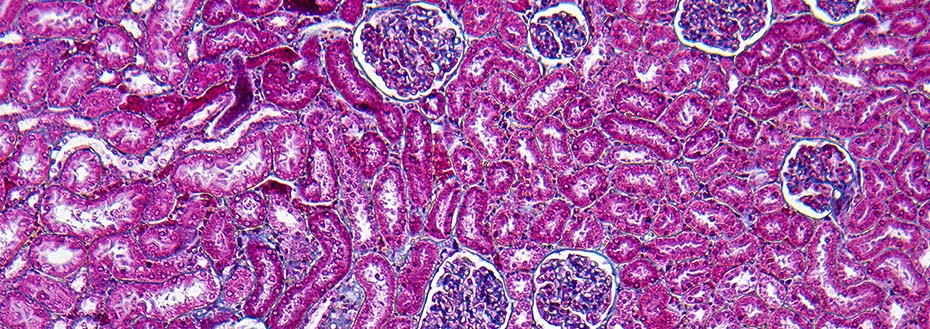

Human kidney cortex section showing Bowman capsules and glomerulus at magnification X100.

This magnified image shows the kidney cortex, the outer layer of the kidney. Dr. Rupali Avasare and her team use human bio-samples to study how autoimmune kidney disease develops.